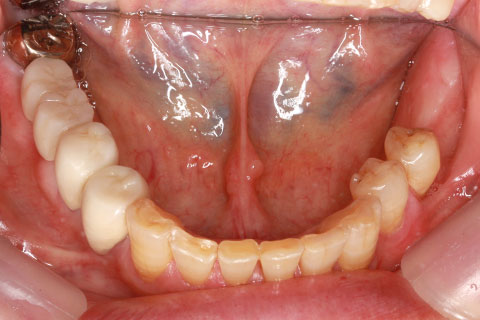

• 症例3

治療前

インプラント埋入時

治療後

年齢・性別

60歳男性

治療期間

2ヶ月

抜歯

なし

治療費

61.6万円

備考

右下6.7欠損

治療内容

右下6.7欠損部にインプラント埋入

施術の副作用(リスク)

オペによる知覚障害。インプラントによる歯肉炎。インプラント脱落。